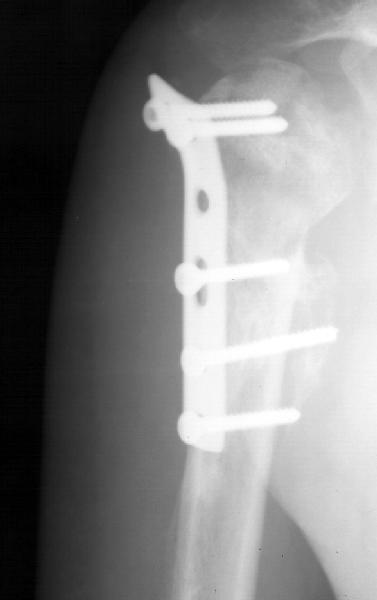

Мужчина 25 лет 16 августа 2002 г. в автоаварии получил перелом шейки плеча (снимок 1); 5 сентября в городской больнице выполнен остеосинтез пластинкой (снимок 2).К настоящему времени попал к нам на разработку ввиду выраженной контрактуры плечевого сустава. В течение последнего месяца беспокоят умеренные боли в области плечевого сустава, усиливающиеся при разработке, еще и торчит край пластинки. Нынешняя рентгенологическаякартина на снимках 3 и 4. Головка плеча уменьшается, сращение сомнительное.Кроме удаления пластинки, что еще на сегодня целесообразно сделать?Заранее спасибо.

2.Пластинка , на мой взгляд, худшее решение для перелома шейки плеча. Сама пластинка слишком груба и массивна, целая слесарня в очень чувствительной для повреждений суставе.

Переломовывих плеча сложная проблема и технически не уверен как для коллег, но для меня сколько я не встречался, технически сложно *вытянуть* вывихнутую головку из-под впадины. Последнее время не применяю пластины для фиксации перелома, а использую спицы и проволочную петлю (тем более часто и густо спонгиозные винты не держатся в головке прочно).